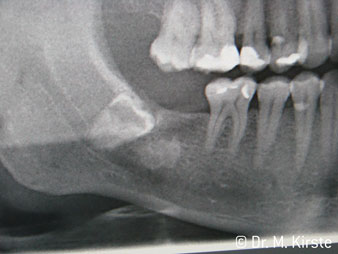

Угол 45° наконечника был выбран специально с учетом широкого круга преимуществ. Коллеги, которые работают в хирургии, и для которых этот наконечник был изначально создан, быстро оценят возможность эффективно работать в очень стесненном пространстве. В частности, при удалении зуба мудрости (рис. 2) не нужно сильно раздвигать мягкие ткани в области щеки (рис. 3). Конструкция головки наконечника в сочетании с небольшим поворотом головки во время препарирования позволяет быстро и безопасно выполнять работу в области задних коренных зубов.

Угловой наконечник с углом 45° очень удобно держать в руках. Вы почти сразу отметите, что рабочая головка имитирует угол наклона вашего указательного пальца, поэтому нужное движение легко переносится на пару воображаемых сантиметров параллельно кончику (рис. 1)".